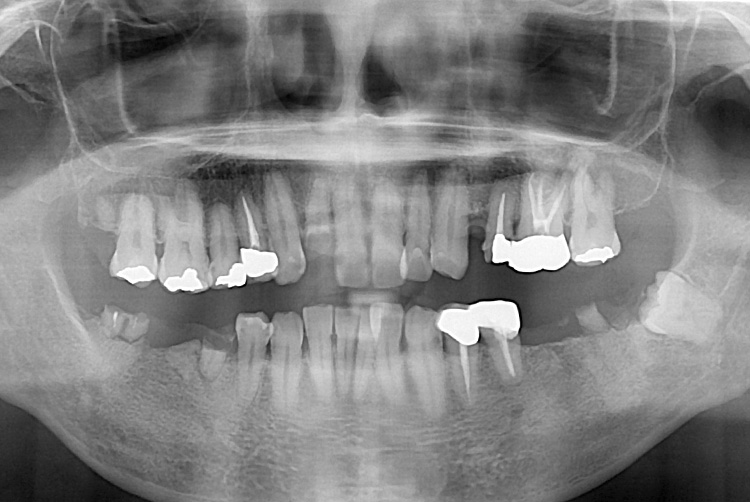

[임플란트] 임플란트

치료전 : 2018-05-12